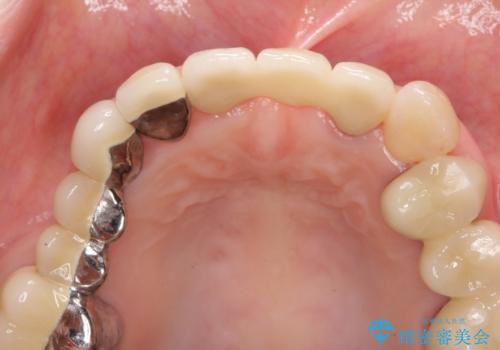

前歯ブリッジのやりかえ

歯肉縁下カリエスも認められるため、挺出を行いセラミックブリッジを審美的に新製します。

- 47万円(仮歯×3・ファイバーコア×2・ジルコニアクラウン×3 歯の挺出)費用は治療当時の料金となります

虫歯が深くなった場合、挺出や歯周外科を行い歯周組織の状態を改善することでより安定した状態で予知性の高いセラミックブリッジを製作することが可能となります。